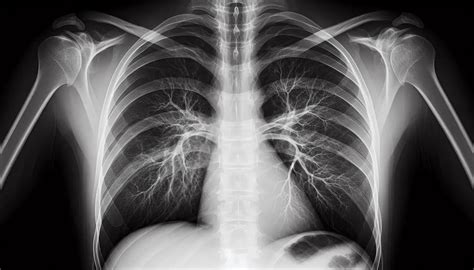

Diagnóstico Pulmonar

En el diagnóstico pulmonar, las áreas de radiolucencia en las radiografías de tórax pueden indicar la presencia de enfermedades como enfisema, neumotórax o neumonía. El enfisema pulmonar, una enfermedad caracterizada por el daño a los alvéolos, muestra un aumento de la radiolucencia debido a la destrucción del tejido pulmonar y el aumento del espacio aéreo.